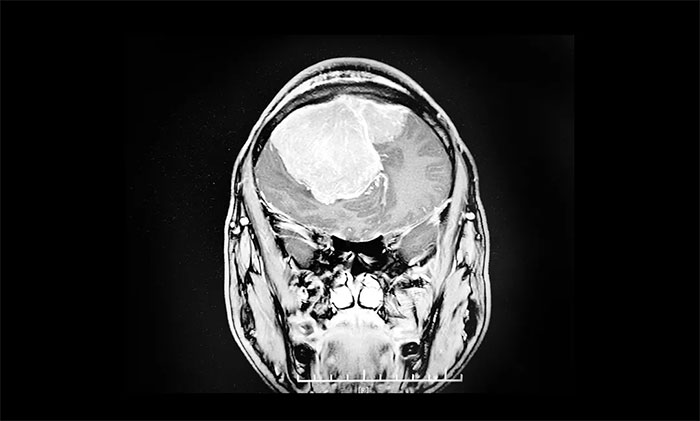

藍(lán)十字為張先生制定了詳盡的檢查計(jì)劃,其中頭顱MRI提示,雙側(cè)額部見一團(tuán)塊狀異常信號(hào)病灶,腫塊跨中線生長(zhǎng),周圍可見大片狀水腫信號(hào),雙側(cè)側(cè)腦室受壓明顯、移位變形,中線結(jié)構(gòu)左側(cè)偏移。臨近額骨骨質(zhì)破壞。

潘仁龍主任、顧國(guó)山教授、吳治群博士經(jīng)過多次會(huì)診討論最終得出:患者腦部腫瘤是雙側(cè)矢狀竇旁腦膜瘤,11cm的瘤體已覆蓋整個(gè)額部。且患者腦疝形成,手術(shù)指征明確,需立即進(jìn)行手術(shù),切除瘤體。

▲ 雙側(cè)矢狀竇旁腦膜瘤,跨中線生長(zhǎng)